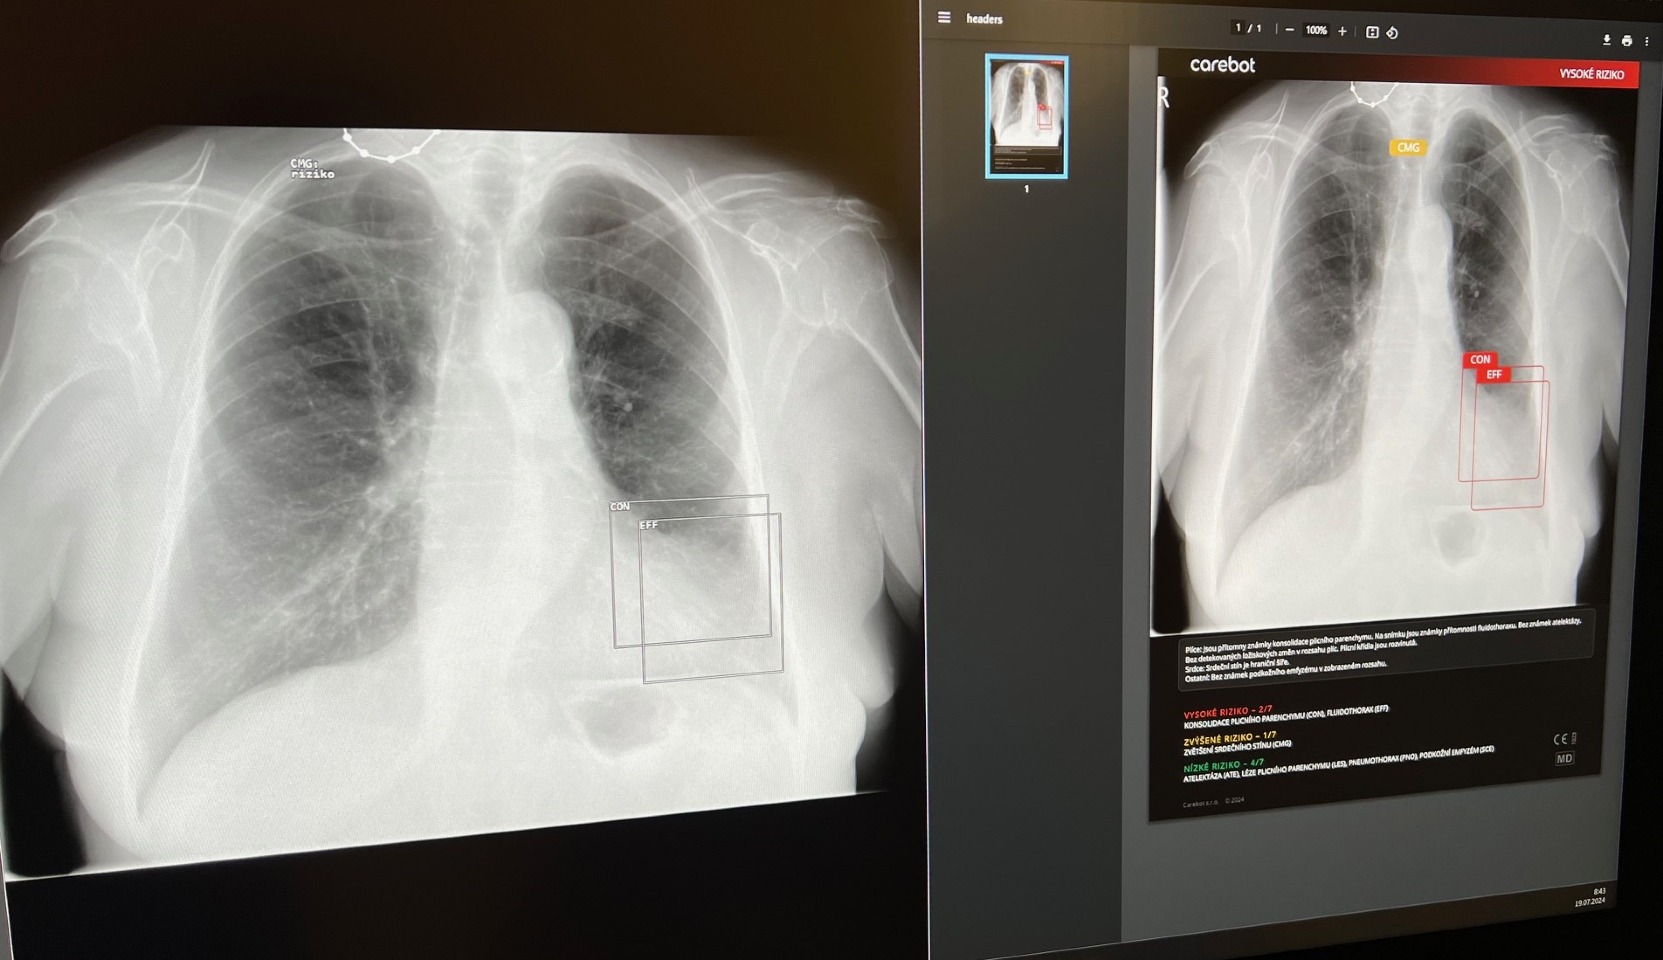

Umělá inteligence (AI) přináší revoluční změny do medicíny. V posledních letech se stává klíčovým faktorem v diagnostice a léčbě nemocí. Jedním z příkladů, jak AI mění zdravotnickou praxi, je systém CARE BOT, který se testuje i na radiologickém oddělení v Nemocnici Tábor, a.s.  Představme si, jaké jsou jeho hlavní výhody a jaký dopad má na péči o pacienty.

CARE BOT, je český projekt, který využívá AI k analýze rentgenových snímků plic. Jeho hlavním cílem je urychlit diagnostiku a zlepšit péči o pacienty. Díky pokročilým algoritmům dokáže CARE BOT rychle identifikovat patologie, jakou jsou nádory, záněty nebo plicní onemocnění. Lékaři mohou lépe plánovat léčbu a minimalizovat lidské chyby. Pro pacienty to znamená větší šanci, že se onemocnění rozpozná včas a zahájí se správná léčba. Počet radiologických vyšetření neustále roste, ale počet lékařů zůstává téměř stejný. Umělá inteligence je proto žádaným partnerem, díky kterému bude lékař schopen zvládnout velký počet vyšetření v požadované kvalitě.